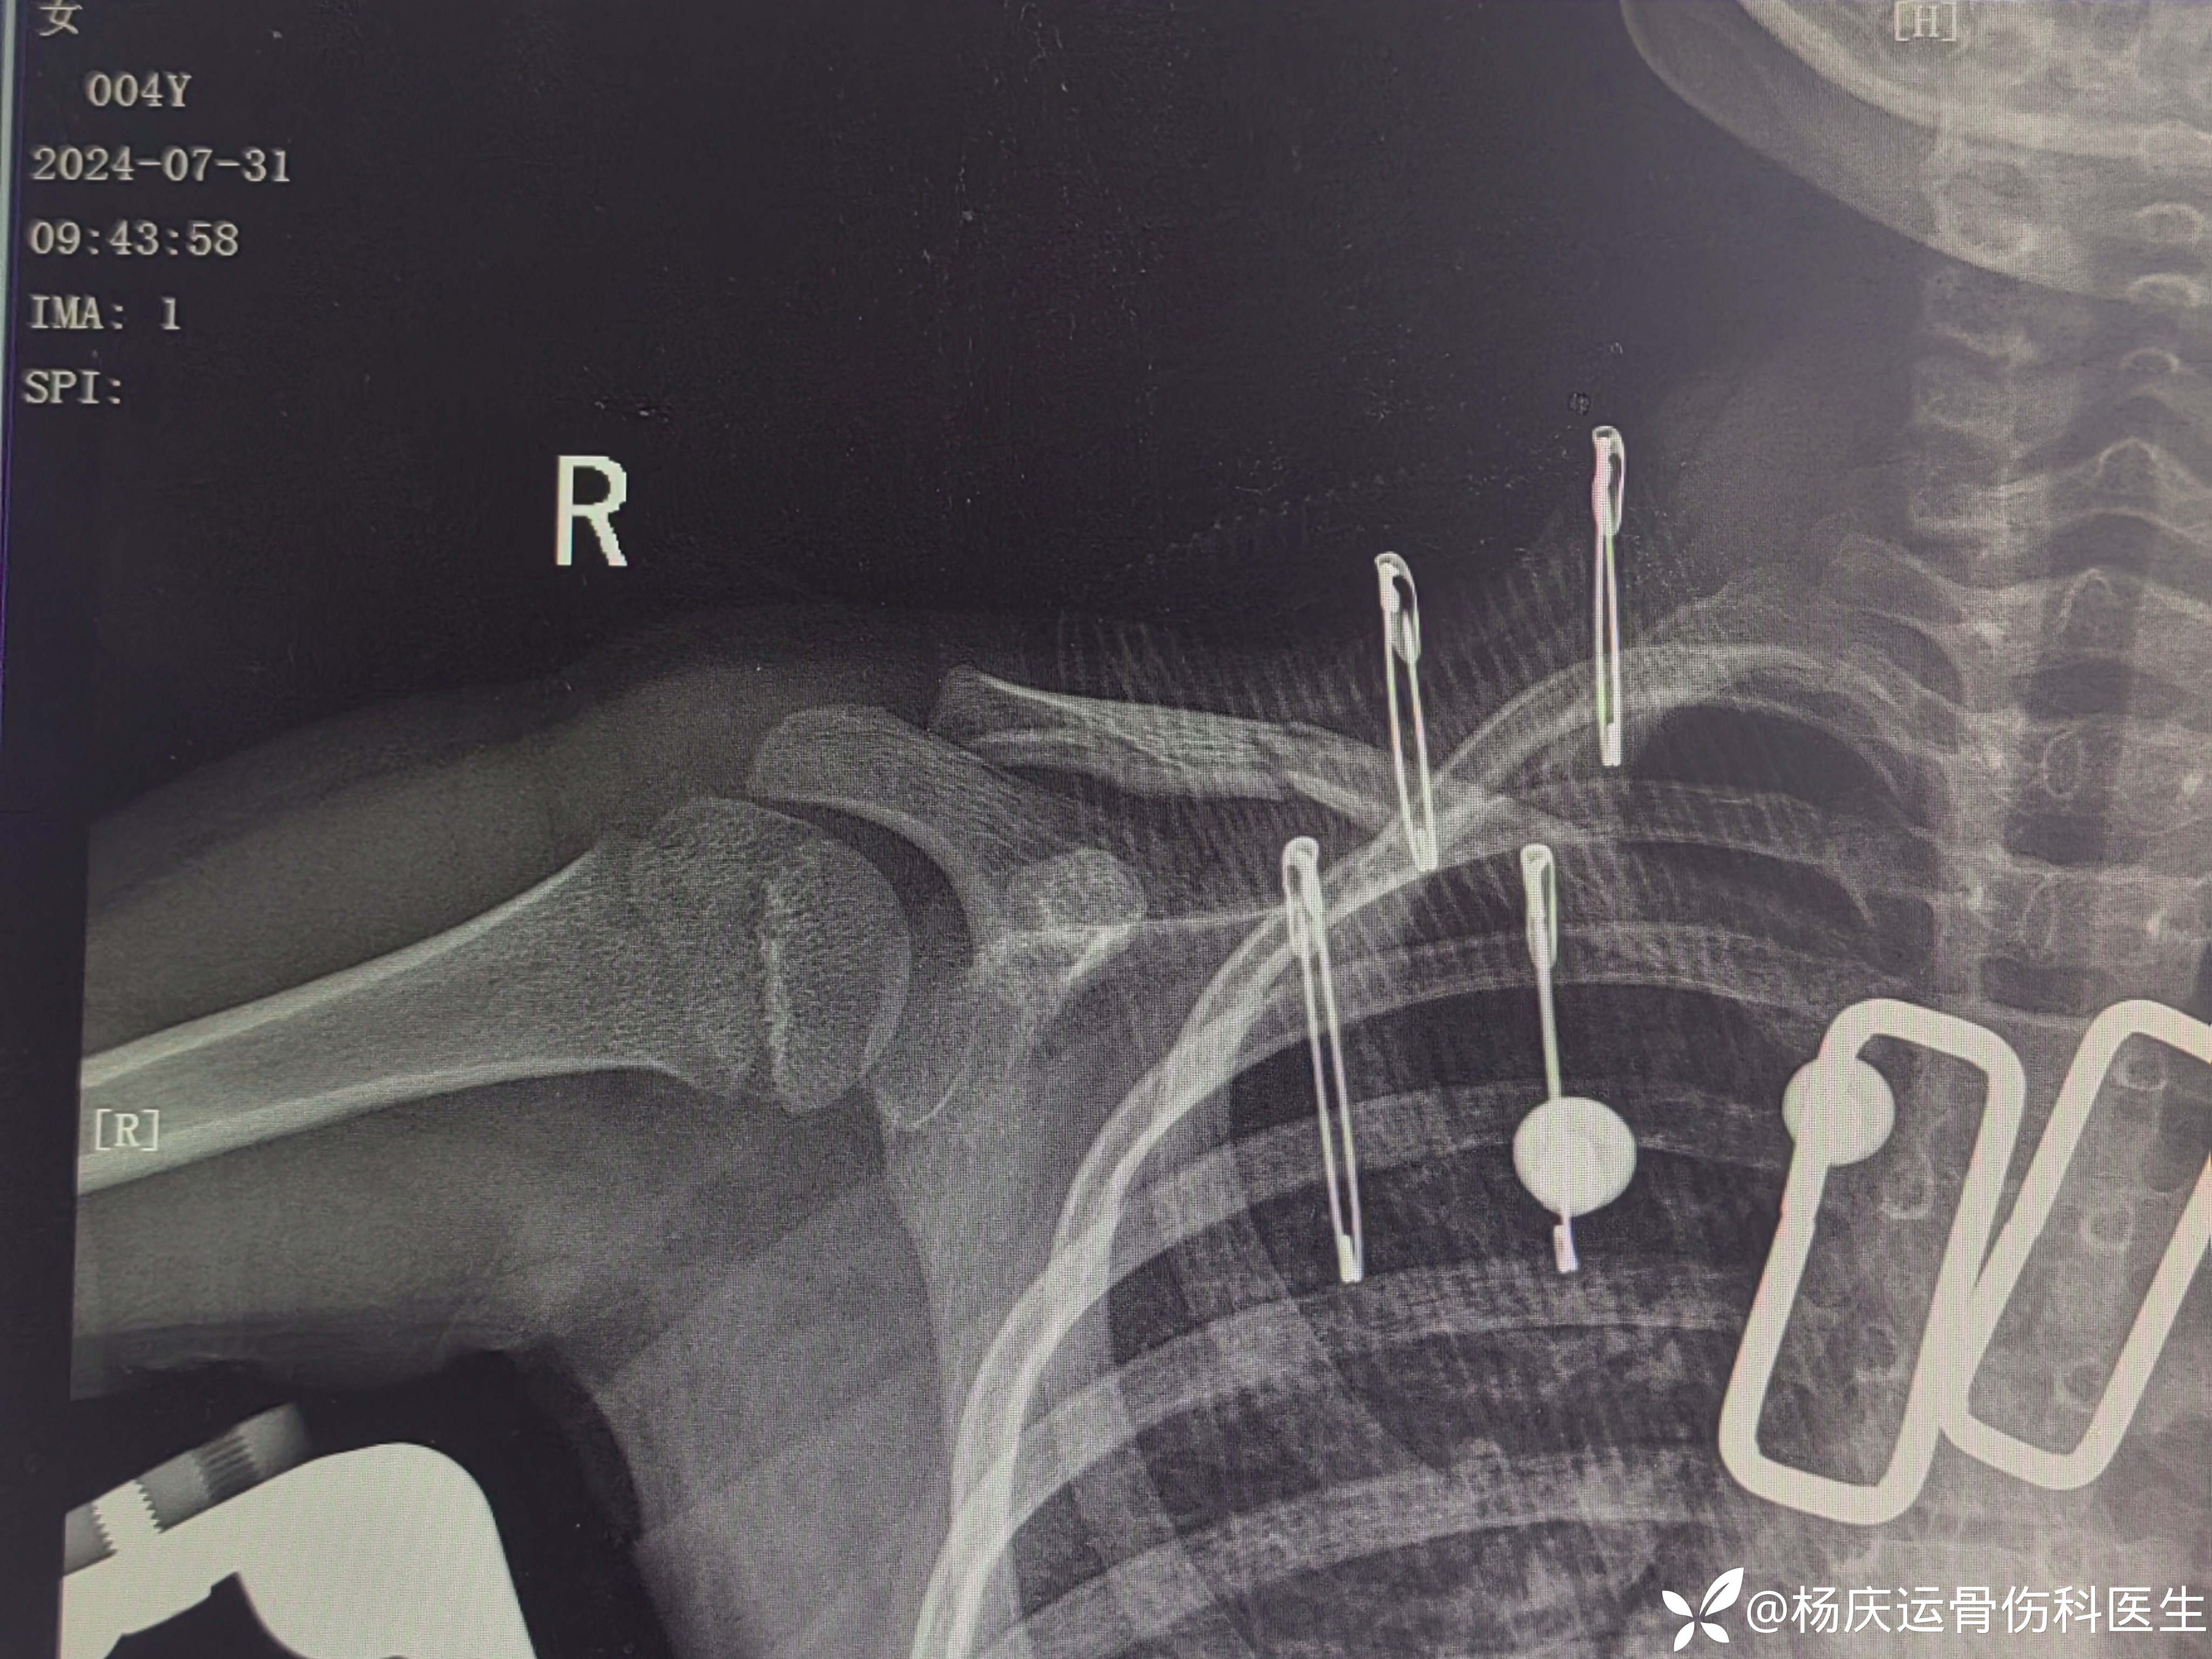

更换外展架后